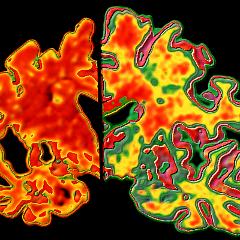

Le géant pharmaceutique américain Pfizer a annoncé, le 6 janvier, qu'il abandonnait la recherche de développement de médicaments pour les maladies neurodégénératives comme la maladie d'Alzheimer et la maladie de Parkison.